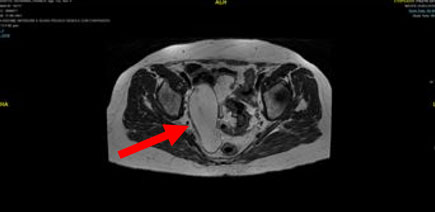

Contrast-enhanced abdominal CT and MRI scans revealed significant thickening and dilation of the appendix (Figure 1 and Figure 2). Post-contrast imaging demonstrated slight enhancement of the appendiceal wall. Pathological analysis confirmed the presence of LAMN (Figure 3). Laparoscopic surgery was performed, revealing a markedly dilated appendix (Figure 4). A linear cutter/stapler was used to perform a laparoscopic ileocecal resection. The resected appendix measured 15 cm in length and 4 cm in width. Postoperative pathology confirmed tumor invasion throughout the appendix, with mucin accumulation observed in the apical portion and within the subserosal (SS) layer. The resection margins were negative for tumor involvement. The patient received symptomatic and supportive care, including nutritional therapy, without the need for antibiotic therapy. She was discharged on postoperative day 4 without complications such as abdominal bleeding, intestinal obstruction, or incision infection. During an outpatient follow-up in December 2024, routine blood tests, biochemical analyses, tumor marker assessments, and chest and abdominal CT scans revealed no evidence of recurrence.

Figure 2: MRI scan confirming thickening of the appendix.

Share Image: